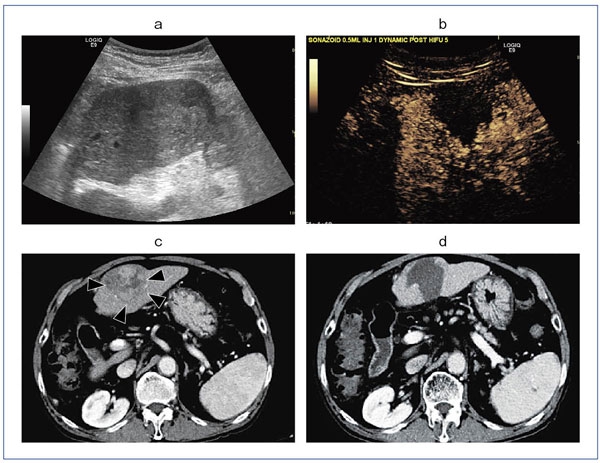

写真のキャプションを入力します。ガンの化学療法は様々ありますが,当研究室ではいわゆるケモセラだけでなく,PDTや放射線療法を利用した「物理療法」のための制がん剤の開発を行っています。ポルフィリンは腫瘍集積性を示す化合物ですが,高い集積性というわけではありません。また,直接抗がん作用を示すわけではありません。PDT(Photo Dymanic Therapy)は,腫瘍に集積したポルフィリンの光触媒作用を利用して一重項酸素を発生させ,周辺の腫瘍細胞を破壊するというものですが,レーザー照射が可能な表面に露出した腫瘍にしか利用できないという欠点があります。当研究室の今の目標は,SDT(Sono Dymanic Therapy)のガンに対する実用化です。SDTとは,レーザーではなく超音波により腫瘍細胞を破壊しようとする治療法です。超音波はエコーなどで知られているとおり,腫瘍の患部を特定することができます。その場合は超音波は散乱するように放射するのですが,その患部に超音波の焦点を当てると腫瘍細胞は破壊可能になります。現在は,HIFUという名称で超音波によるガン治療は行われていますが,破壊作用を増幅する超音波増感剤はまだほとんど知られていません。この開発に成功すれば,ガン治療の大きな一歩になると考えています。

当研究室の目的は,腫瘍集積性を持つPDTまたはSDTの増感剤となる化合物の開発です。増感剤としてはポルフィリンとローズベンガルを用いていますが,最近は腫瘍集積性部位の開発も行っています。SDT増感作用に関しては,まだメカニズムが不明な点が多いのですが,そのメカニズムに関する研究も行っています。